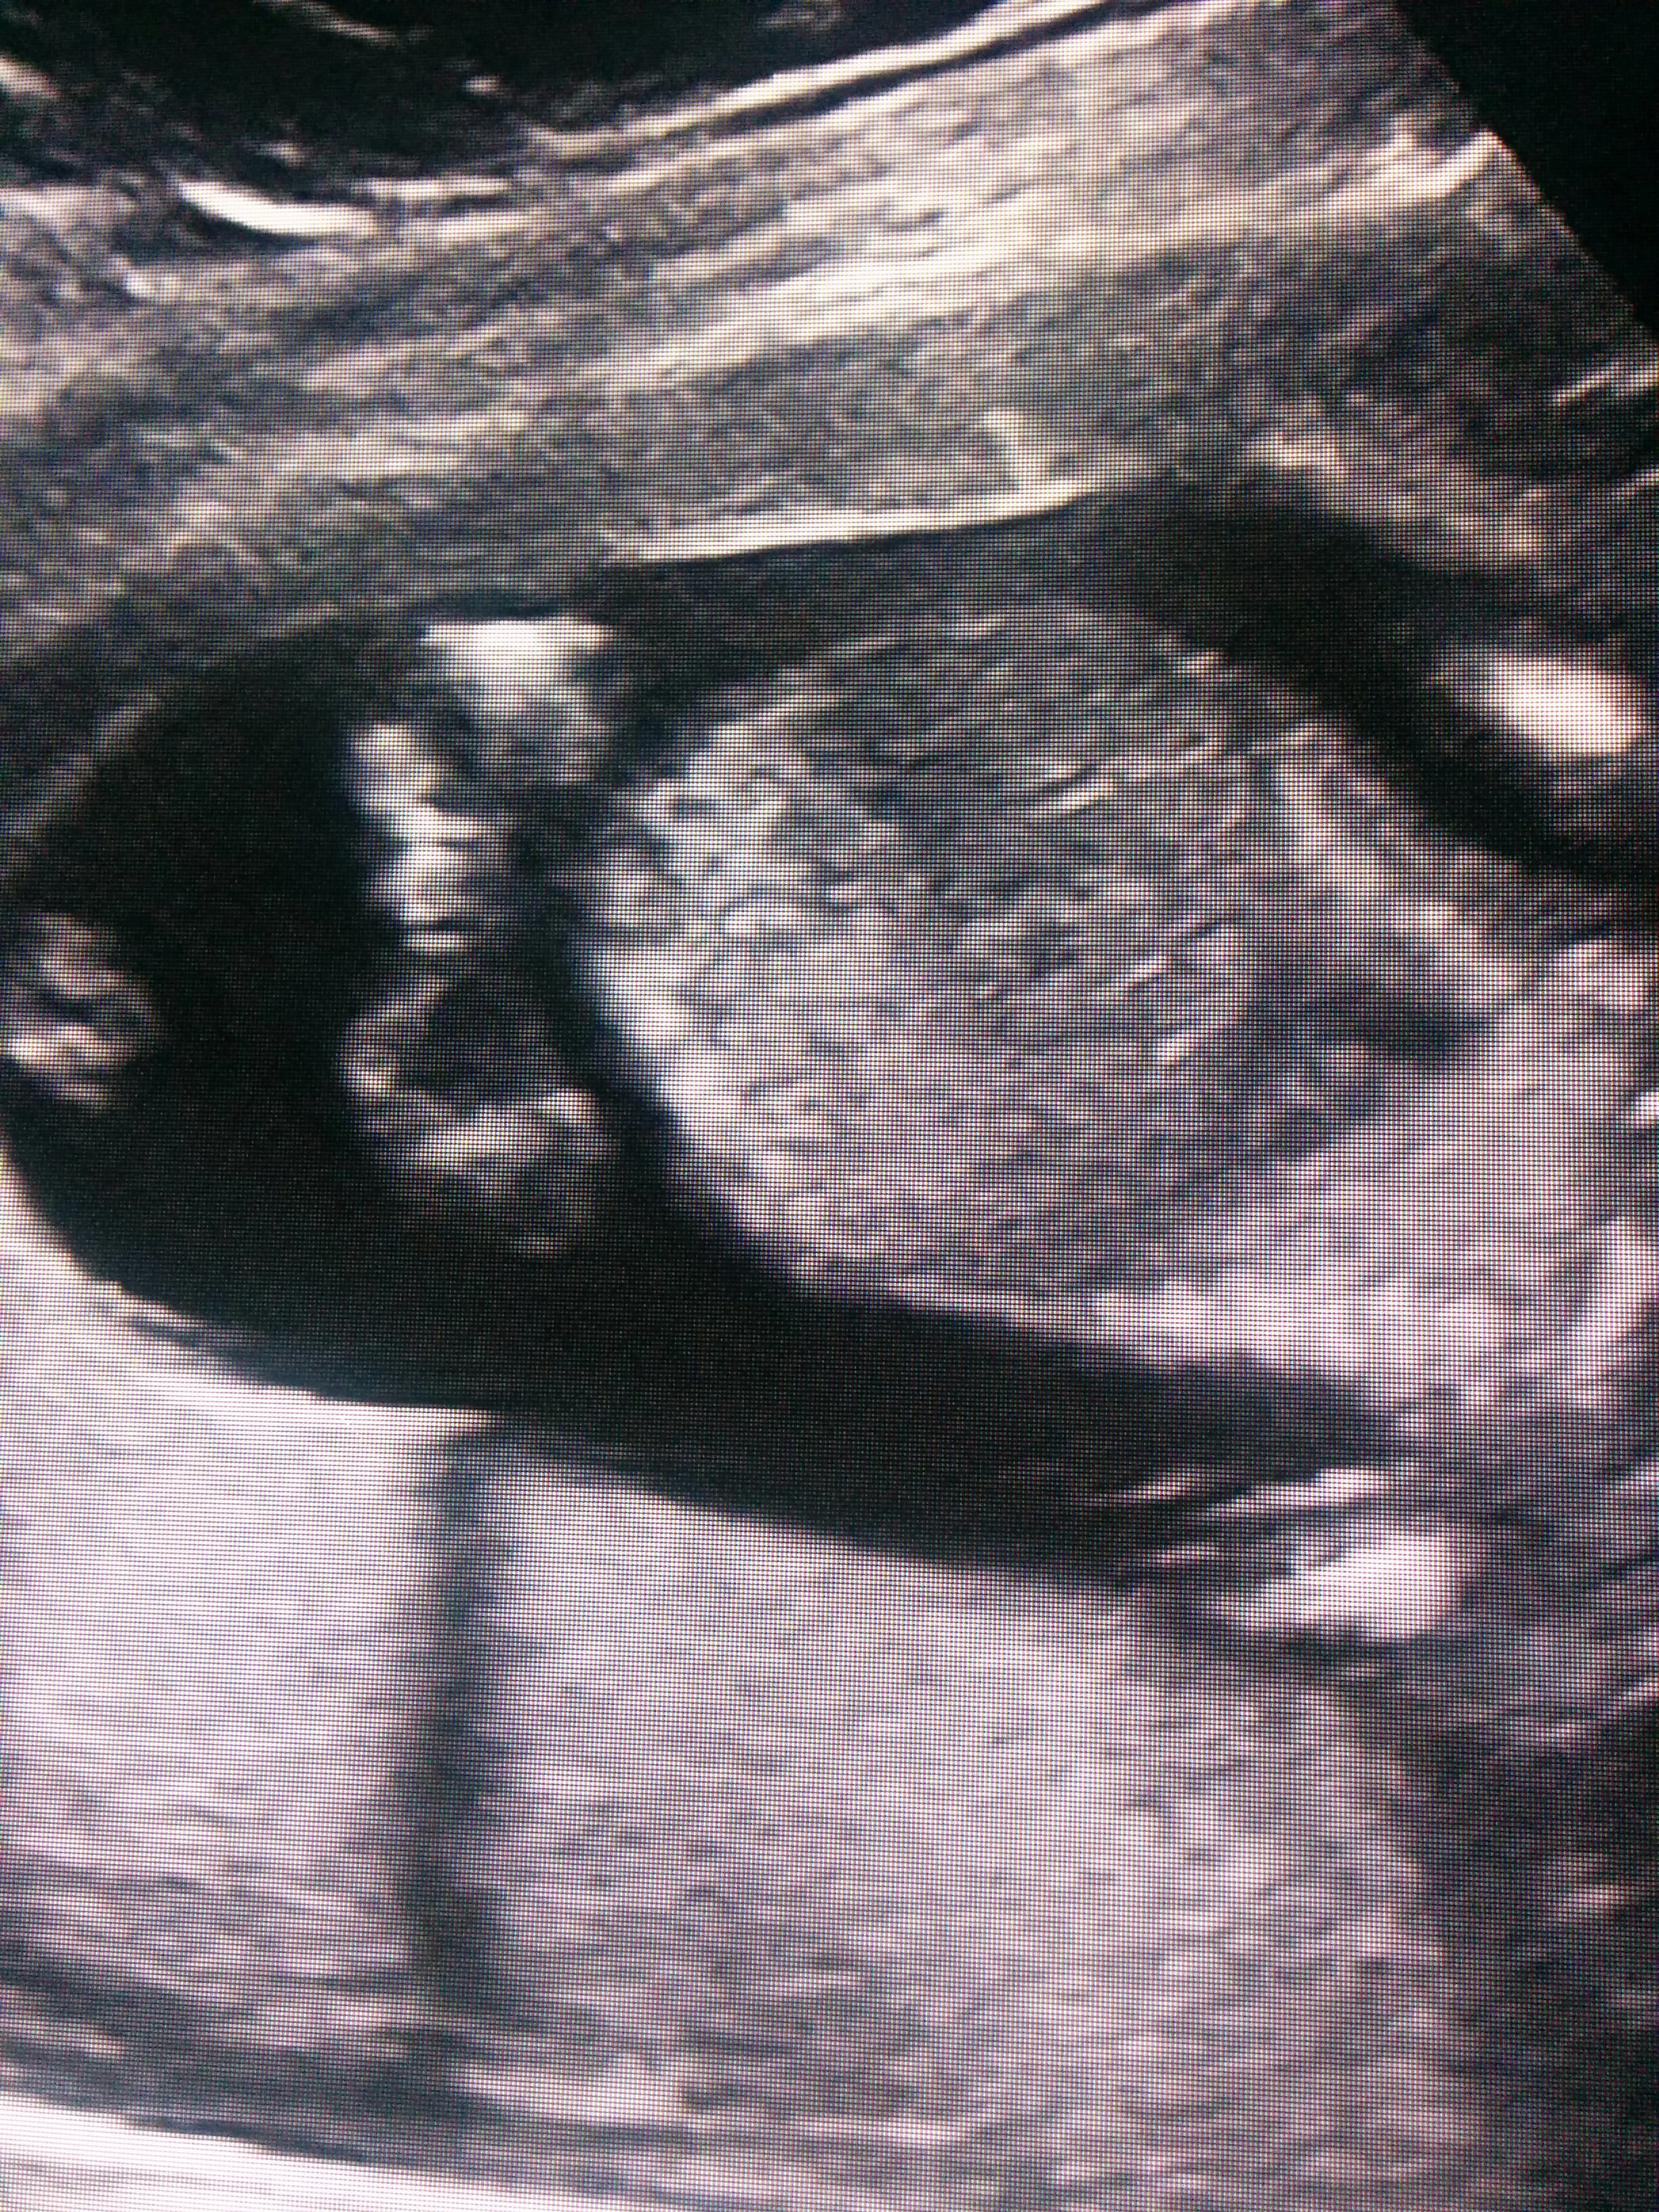

I was 16 weeks 2 days. I know the pic isn't the greatest. Any guesses?Attachment 28571

Tech was unsure leaning towards girl.